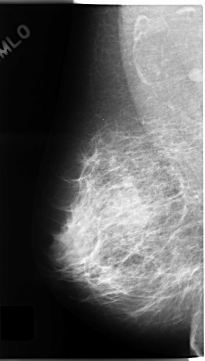

C_0136_1.LEFT_MLO

LEFT_MLO LINES 4728 PIXELS_PER_LINE 2808 BITS_PER_PIXEL 12 RESOLUTION 50 OVERLAY